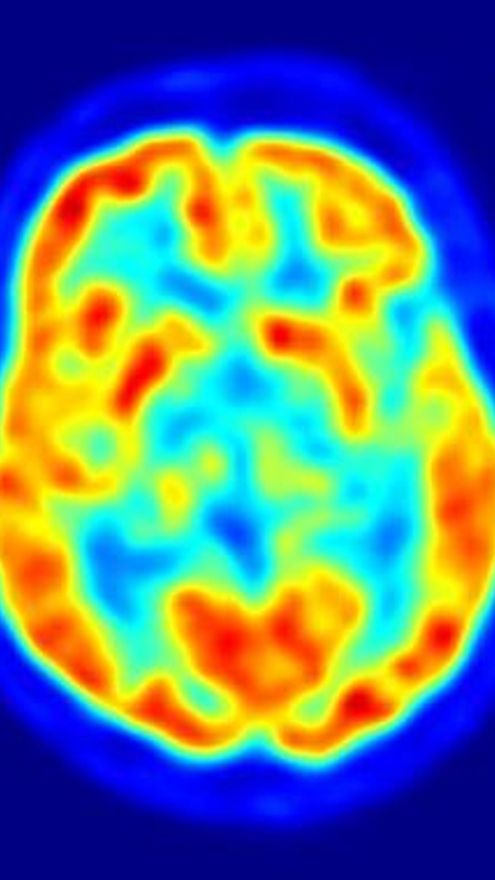

Consiguen convertir células humanas de la piel en neuronas

Científicos de la Universidad de Stanford, en Estados Unidos, han conseguido convertir células de la piel en neuronas en funcionamiento simplemente añadiéndoles cuatro proteínas, mediante un proceso que dura de cuatro a cinco semanas, según los resultados de una investigación que publica 'Nature'.